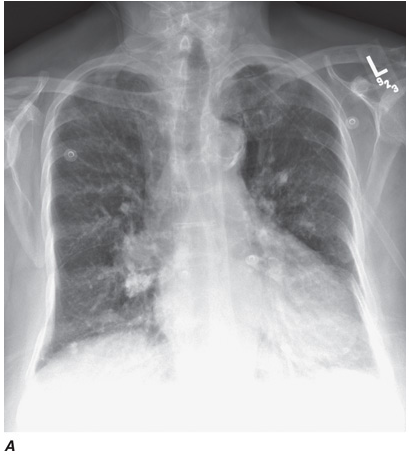

Computed tomography (CT) offers several advantages over routine chest radiography (Figs. C-1A, B and C-2A, B). First, the use of cross-sectional images allows distinction between densities that would be superimposed on plain radiographs. Second, CT is far better than routine radiographic studies at characterizing tissue density, distinguishing subtle density differences between adjacent structures, and providing accurate size assessment of lesions.

CT is particularly valuable in assessing hilar and mediastinal disease (which is often poorly characterized by plain radiography), in identifying and characterizing disease adjacent to the chest wall or spine (including pleural disease), and in identifying areas of fat density or calcification in pulmonary nodules (Figs. C-2A, B). Its utility in the assessment of mediastinal disease has made CT an important tool in the staging of lung cancer, as an assessment of tumor involvement of mediastinal lymph nodes is critical to proper staging. With the additional use of contrast material, CT also makes it possible to distinguish vascular from nonvascular structures, which is particularly important in distinguishing lymph nodes and masses from vascular structures primarily in the mediastinum, and vascular disorders such as pulmonary embolism.